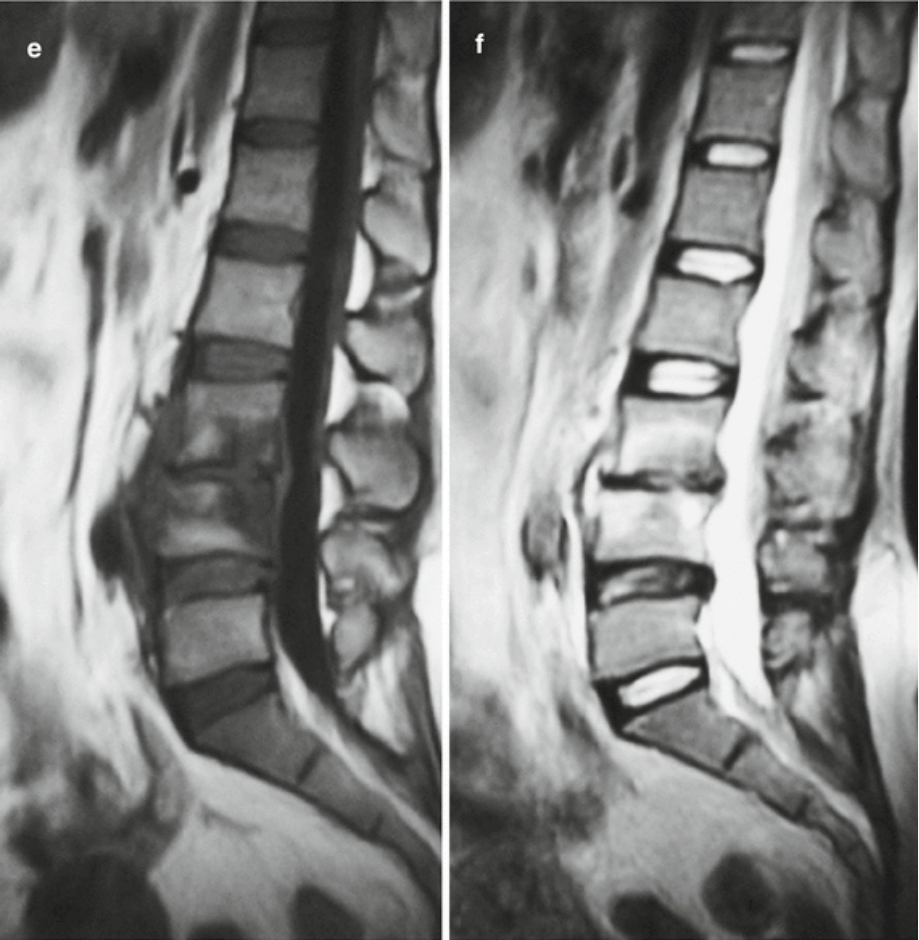

42岁女性,间歇性发热11个月,持续不断的腰痛7个月,双下肢无力1个月入院。体格检查发现L3、L4棘突附近压痛,无放射性疼痛。直腿抬高试验,右腿70,左腿90,双下肢肌肉萎缩。实验室检测WBC 6.61×109L,布鲁氏菌抗体滴度为1:16。影像学表现见下图a~f

图a、b、c、d  CT扫描 显示L4椎体终板多处不规则骨破坏,伴有边缘硬化,无死骨。骨破坏区周围呈花边样骨赘增生,椎体周围软组织肿胀。

图e、 f  MRI成像显示L3和L4椎体长T1和长T2斑块信号,边界不清。L3/L4椎间隙变窄,伴有椎旁软组织肿胀和硬膜囊轻微受压。